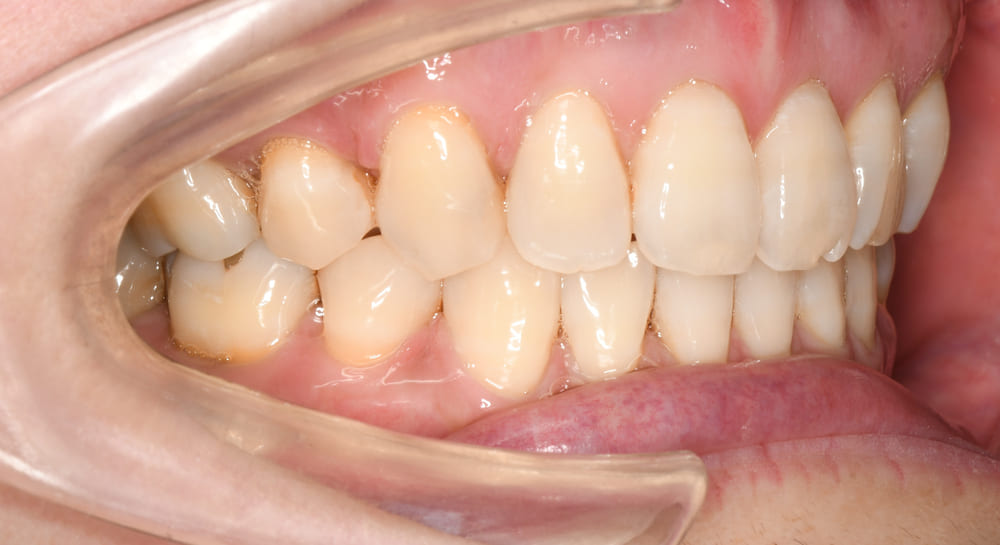

右側です。

上下顎前歯の唇側傾斜が改善され理想的な歯軸傾斜と上下的なかみ合わせを獲得することが出来ました。